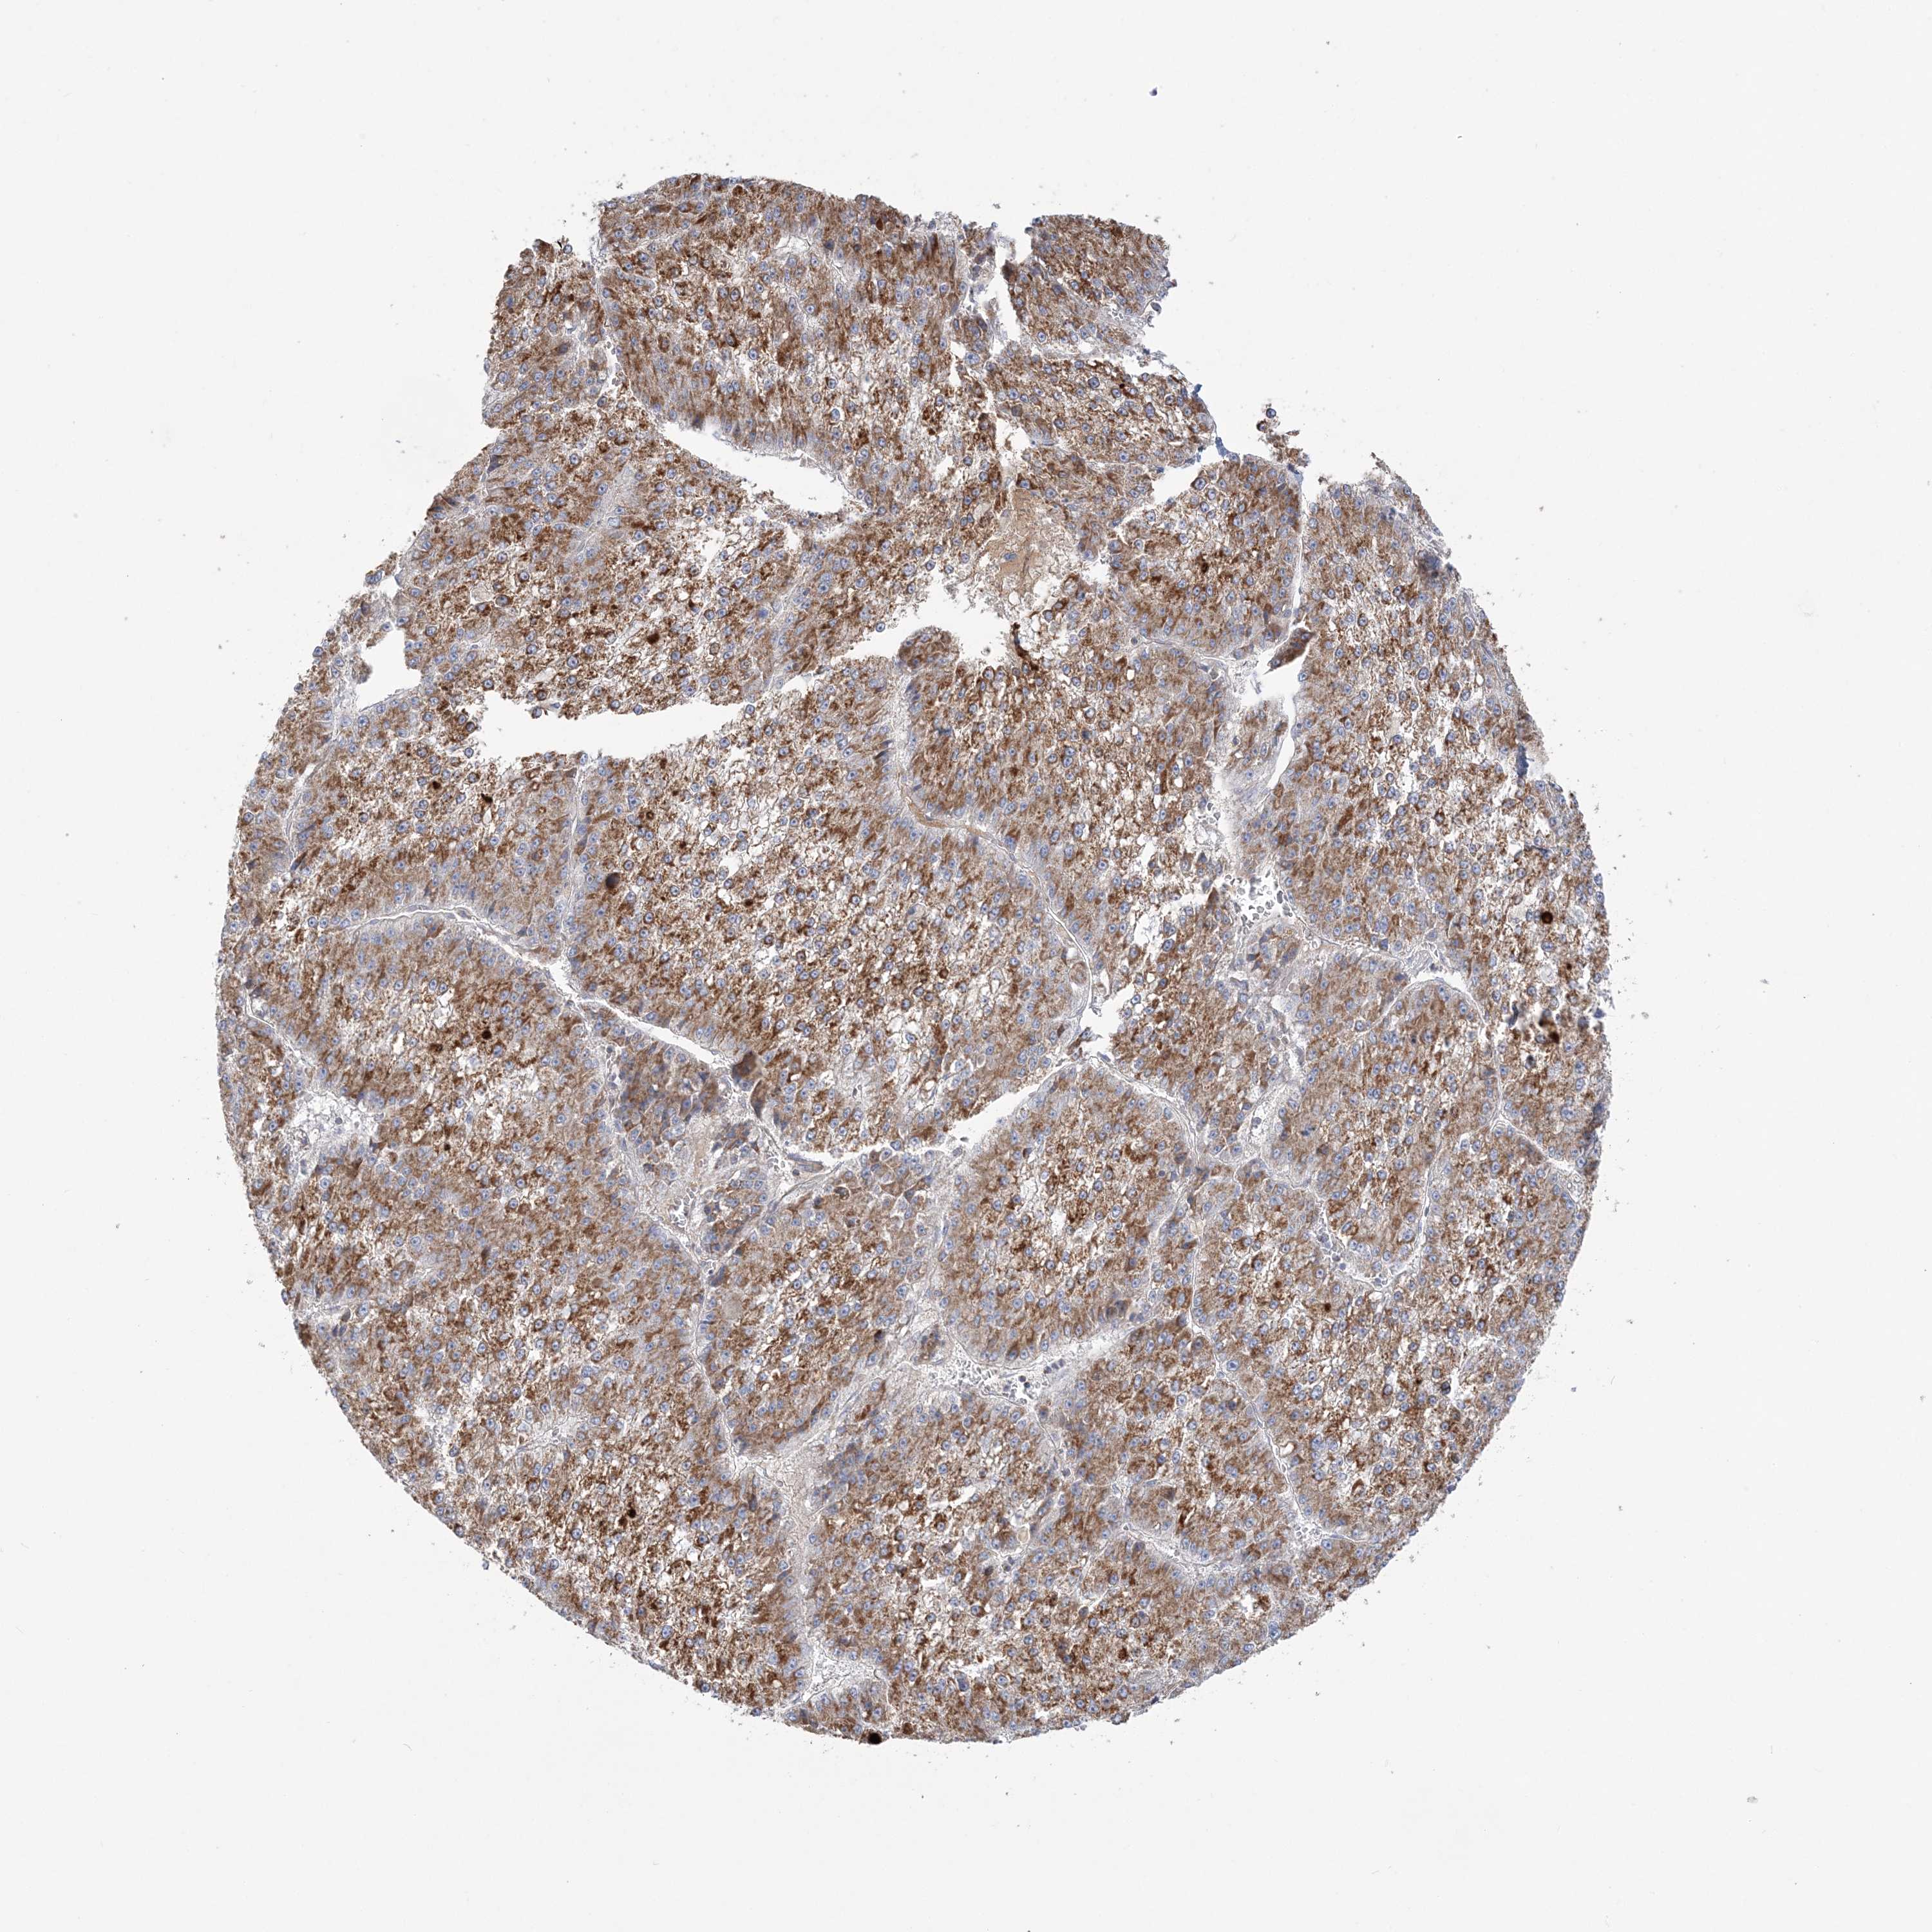

LIVER CANCER - Protein expressioni

A mouse-over function shows sample information and annotation data. Click on an image to view it in a full screen mode. Samples can be filtered based on level of antibody staining by selecting one or several of the following categories: high, medium, low and not detected. The assay and annotation is described here.

Antibody stainingi

Antibody staining in the annotated cell types in the current human tissue is reported as not detected, low, medium, or high, based on conventional immunohistochemistry profiling in selected tissues. This score is based on the combination of the staining intensity and fraction of stained cells.

Each image is clickable and will lead to virtual microscopy that enables deeper exploration of all samples and also displays staining intensity scores, fraction scores and subcellular localization as well as patient and tissue information for each sample.

Antibody HPA036560

Antibody HPA036561

Staining

High

Medium

Low

Not detected

Intensity

Strong

Moderate

Weak

Negative

Quantity

>75%

75%-25%

<25%

None

Location

Nuclear

Cytoplasmic/membranous

Cytoplasmic/membranous,nuclear

Cholangiocarcinoma

Carcinoma, Hepatocellular, NOS